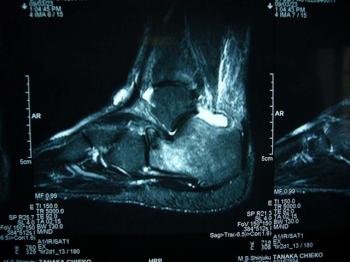

箕山スポーツ医学塾(File №11): 踵骨疲労骨折stress fracture of calcaneus

踵骨体部・隆起部付近での疲労骨折ではなく、頚部に発生した比較的稀な症例

middle age / female / runner

フルマラソン後より右足部外側の疼痛

踵骨前方から立方骨にかけて、軽度腫脹(+)、圧痛(+)、heel squeeze test(‐)、X-ray(n.p.)

左:初診時(n.p.) 右:10週後callus(+)(MRIでhigh intensityのあった後距骨関節面の前方凹部)

踵骨前方に発生した疲労骨折[考察] stress faracture of the anterior portion of the calcaneus [discussion]

この症例の特徴的なalignment

1. high arch

2. inversion & limited motion of subtalar joint(内反で硬い距骨下関節)

発生メカニズム

A) high archのため、踵骨の厚さの無い部位への荷重垂直応力

B) mid stance phase~late stance phaseにおいて、中足部より遠位がhyper-pronation(過回内)の代償運動をすることで、踵骨の前方へ捻れ負荷と立方骨側からの圧力